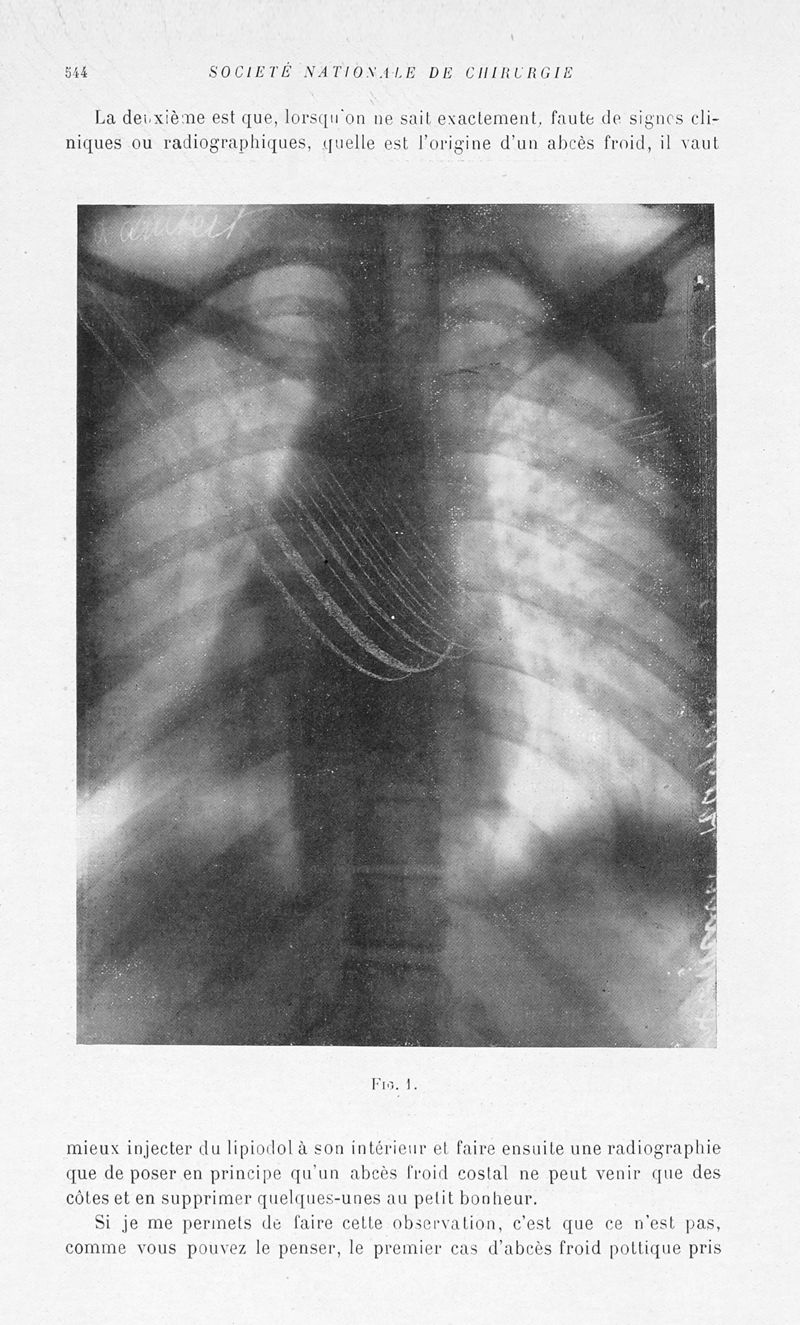

Bulletins et mémoires de la société nationale de chirurgie

Tome LVI, 1930. - Paris : Masson, 1930.